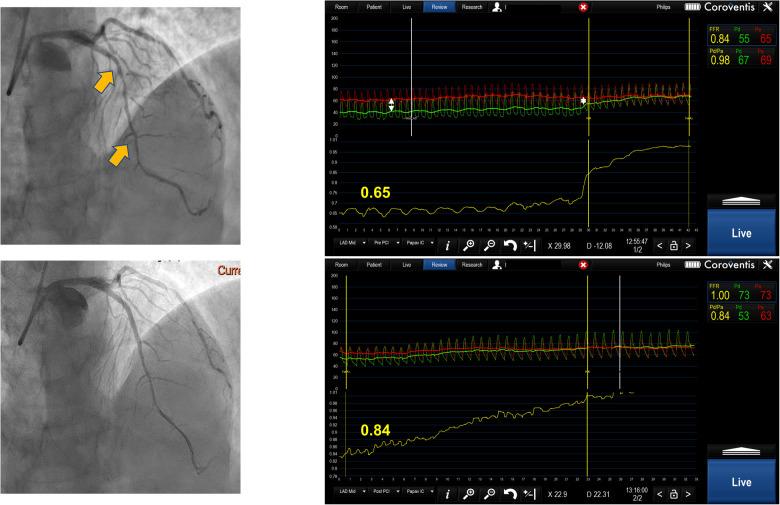

连续狭窄评估——我们能否依赖有创冠状动脉生理学检查?

Atherosclerosis is a widespread disease affecting coronary arteries. Diffuse atherosclerotic disease affects the whole vessel, posing difficulties in determining lesion significance by angiography. Research has confirmed that revascularization guided by invasive coronary physiology indices improves patients' prognosis and quality of life. Serial lesions can be a diagnostic challenge because the measurement of functional stenosis significance using invasive physiology is influenced by a complex interplay of factors. The use of fractional flow reserve (FFR) pullback provides a trans-stenotic pressure gradient (P) for each of the lesions. The strategy of treating the lesion with greater P first and then reevaluating another lesion has been advocated. Similarly, non-hyperemic indices can be used to assess the contribution of each stenosis and predict the effect of lesion treatment on physiology indices. Pullback pressure gradient (PPG) integrates physiological variables of coronary pressure along the epicardial vessel and characteristics of discrete and diffuse coronary stenoses into a quantitative index that can be used to guide revascularization. We proposed an algorithm that integrates FFR pullbacks and calculates PPG to determine individual lesion importance and to guide intervention. Computer modeling of the coronaries and the use of non-invasive FFR measurement together with mathematical algorithms for fluid dynamics can make predictions of lesion significance in serial stenoses easier and provide practical solutions for treatment. All these strategies need to be validated before widespread clinical use.

动脉粥样硬化是一种影响冠状动脉的广泛疾病。弥漫性动脉粥样硬化疾病累及整个血管,通过血管造影确定病变的重要性存在困难。研究证实,以有创冠状动脉生理学指标为指导的血运重建可改善患者的预后和生活质量。串联病变可能是一个诊断挑战,因为使用有创生理学方法测量功能性狭窄的重要性会受到多种因素复杂相互作用的影响。使用血流储备分数(FFR)回撤可为每个病变提供跨狭窄压力梯度(P)。有人主张先处理P值较大的病变,然后再重新评估另一个病变的策略。同样,非充血指标可用于评估每个狭窄的作用,并预测病变治疗对生理学指标的影响。回撤压力梯度(PPG)将沿心外膜血管的冠状动脉压力生理变量以及离散和弥漫性冠状动脉狭窄的特征整合为一个可用于指导血运重建的定量指标。我们提出了一种算法,该算法整合FFR回撤并计算PPG,以确定单个病变的重要性并指导干预。冠状动脉的计算机建模以及无创FFR测量与流体动力学数学算法的结合,可以使串联狭窄病变重要性的预测更容易,并为治疗提供切实可行的解决方案。所有这些策略在广泛临床应用之前都需要进行验证。